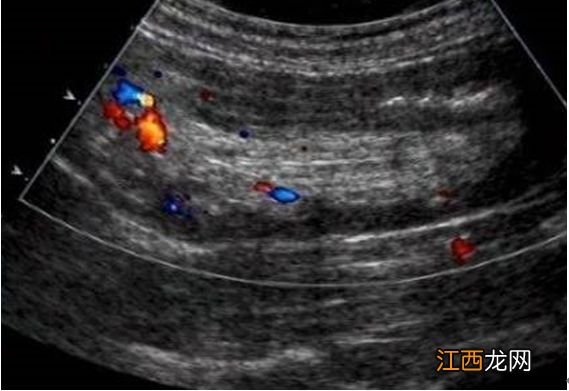

(1)腹部B超:横断扫描可见“同心圆”或空气“靶环状”图像(如下图1所示);纵断扫描可见“套筒征”(如下图2所示) 。

图1示:肠套叠的同心圆征

图2示:肠套叠的套筒征